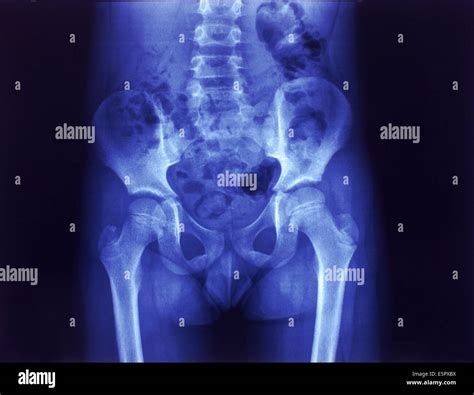

Interpreting a Normal Hip X Ray

Interpreting a Normal Hip X Ray involves evaluating the images for various features and abnormalities. Key aspects that radiologists look for include:

• The alignment and position of the femoral head within the acetabulum.

• The presence of fractures, dislocations, or other bony abnormalities.

• The condition of the joint space, which can indicate the presence of osteoarthritis or other degenerative changes.

• The presence of any soft tissue swelling, calcifications, or other abnormalities.

Radiologists use specific terminology and measurements to describe the findings on a Normal Hip X Ray. Some common terms and measurements include:

Term/Measurement Description

Acetabular Index Angle between the acetabular roof and the horizontal plane, used to assess hip dysplasia.

Center-Edge Angle Angle between the vertical line through the center of the femoral head and a line from the center to the lateral edge of the acetabulum, used to assess hip coverage.

Shenton’s Line A smooth curve formed by the inferior border of the superior pubic ramus and the inferior border of the femoral neck, used to assess hip dislocation.

Common Findings on a Normal Hip X Ray

A Normal Hip X Ray can reveal a variety of findings, ranging from normal anatomy to significant abnormalities. Some common findings include:

• Normal hip anatomy, with well-aligned bones and joints.

• Fractures of the femoral neck, intertrochanteric region, or acetabulum.

• Hip dislocations, which can be anterior, posterior, or central.

• Osteoarthritis, characterized by joint space narrowing, osteophyte formation, and subchondral sclerosis.

• Hip dysplasia, with a shallow acetabulum and abnormal femoral head coverage.

• Avascular necrosis, which can appear as areas of bone density changes and collapse.